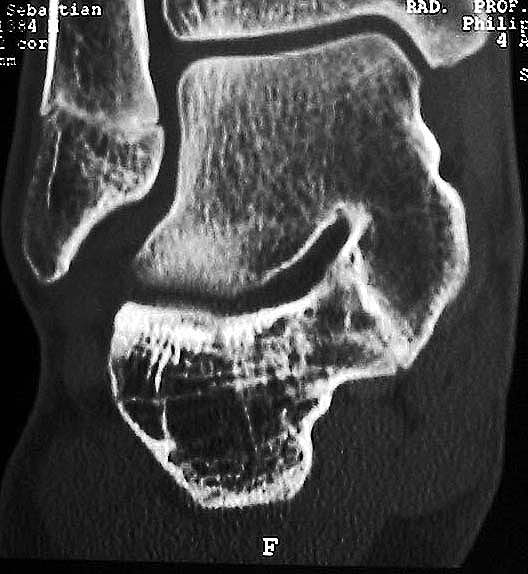

MRT und CT konkurrieren in der Fein-Darstellung der Knochenbrücke, der Beurteilung der nichtbetroffenen Anteile des Subtalargelenkes und der Sekundärveränderungen. Das MRT bietet den Vorzug, bindegewebige und knorpelige Strukturen (Abb. 2) und bei Einsatz von Kontrastmittel auch knöcherne Aktivierungsphänomene genau abzubilden; die knöcherne Feinstruktur und genaue Ausdehnung dagegen ist mit dem Dünnschicht-CT wesentlich exakter darstellbar (Abb.3). In manchen Fällen ist eine 3-D-Rekonstruktion des CT hilfreich. Besonders wichtig ist eine geeignete Schichtebenen-Wahl:

Die zweite wichtige Form tarsaler Coalitiones findet sich im medialen Bereich des Subtalargelenkes, am häufigsten unter Einbeziehung der medialen, mittleren Facette des talocalcanearen Gelenkes (Abb. 9). Die Ausdehnung der zunächst fibrösen, später zunehmend verknöcherten Brückenbildung kann sehr unterschiedlich Anteile der hinteren Kammer des unteren Sprunggelenkes mitumfassen; auch rein dorsomediale Formen ohne Einbeziehung der medialen Facette werden beobachtet (Abb. 2) 67 (Hamel 2008).

Diagnostisch sollte neben Röntgenübersichtsaufnahmen (indirekte radiologische Zeichen: Dorsaler Traktions-Osteophyt am Taluskopf, „talar beaking“; kontinuierliche Linie der Trochlea-tali-Kontur übergehend in die Sustentaculum-tali-Kontur, „C-Zeichen“ (Abb. 11) 10) immer die dreidimensionale Bildgebung eingesetzt werden. Das MRT (mit Kontrastmittel) kann die Struktur der Brückenbildung und z.B. die Qualität des Restgelenkes (Knorpel-Dicke) besonders gut abbilden; das Dünnschicht-CT zeigt die knöcherne Feinstruktur im Bereich der Coalitio und den oft sehr schrägen Spalt-Verlauf im Frontalschnitt dagegen häufig genauer. Meist findet sich die Überbrückung im Bereich der medialen Facette; die Schichten sollten jedoch bis weit nach dorsal beurteilt werden, da ansonsten dorsomediale Formen übersehen werden können. Rozansky et al 7 unterschieden fünf morphologische Typen auf der Basis von 3-D-CT-Rekonstruktionen. Allerdings ist eine prognostische Zuordnung bisher nicht möglich.